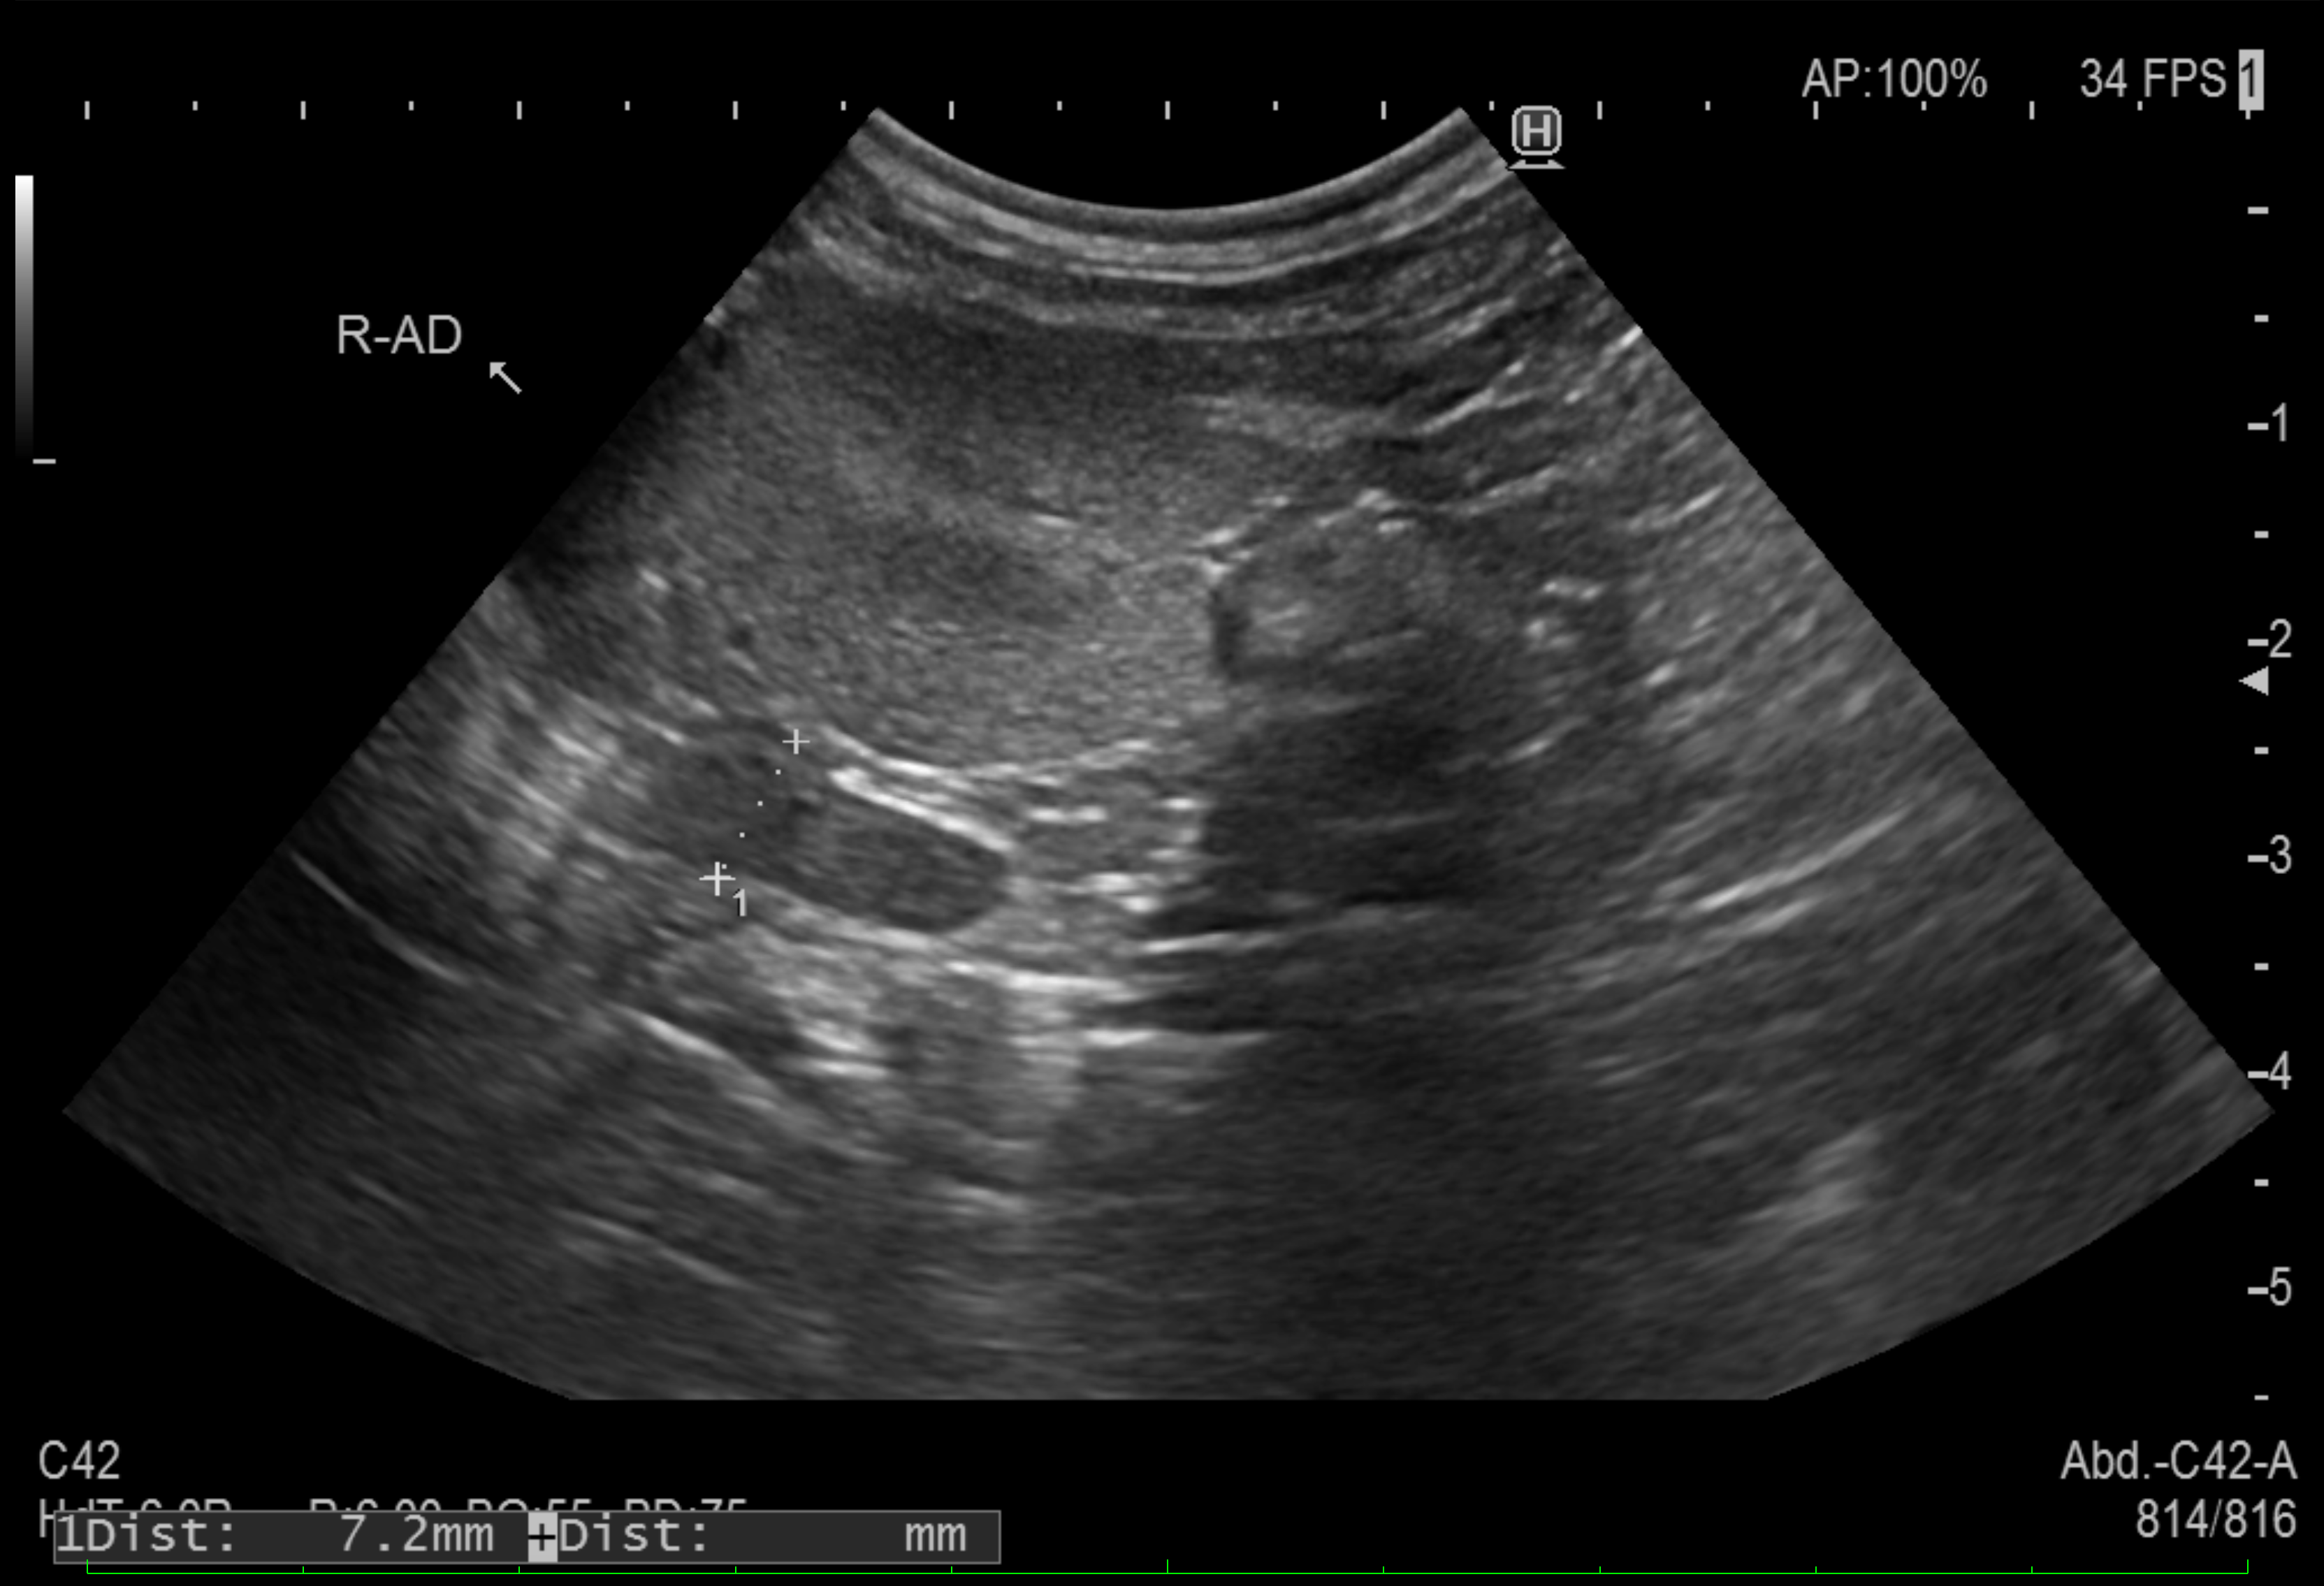

超音波検査では、腫大した副腎が確認できます。

健康な子の場合、副腎の短径の最大径が3〜5mm程度、大型犬では5~8mm程度です。

個体差もありますが、小型犬では6mm、大型犬では10mmを超えていれば副腎過形成と判断します。

7mm程度に軽度腫大した副腎の超音波画像